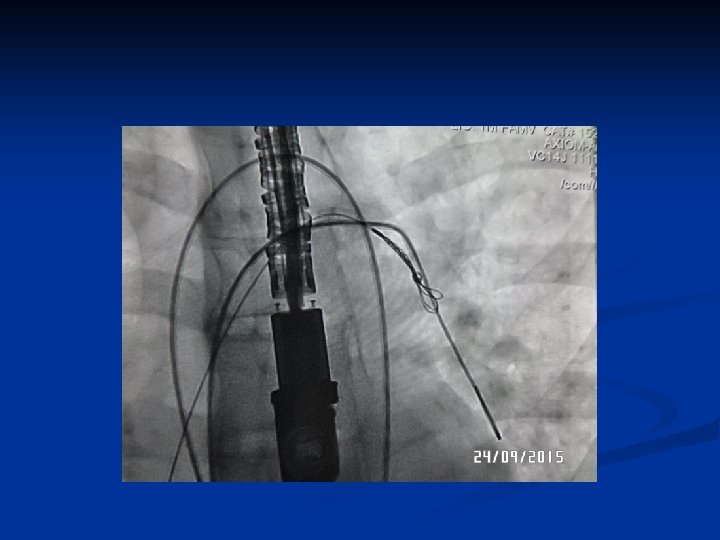

Cat. Diagnostico

Creación Sist. Arterio-Venoso

Control Cierre